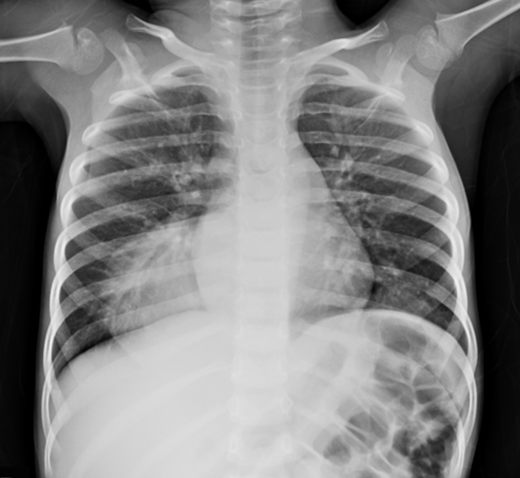

Case report: The use of Venovenous Extracorporeal Membrane Oxygenation in the Treatment of Acute Respiratory Distress Syndrome in Severe Leptospirosis

Fernando de Oliveira e Silva Neto, Renan Gomes Mendes Diniz, Gabriel Cavalcante Lima Chagas, Helen Melo Oliveira Felix, Ana Larissa Pedrosa Ximenes, Bráulio Matias de Carvalho, Fátima Rosane de Almeida Oliveira, Daniel Francisco de Mendonça Trompieri, Juan Alberto Casquillo Meija, Lucia da Conceição Andrade, Elizabeth de Francesco Daher